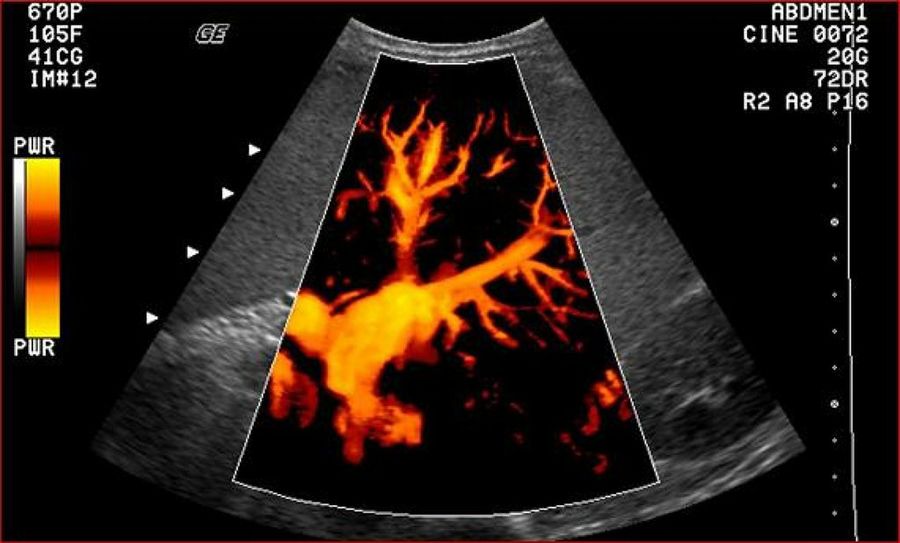

Una ecografía Doppler es un estudio por imágenes que utiliza ondas de sonido para mostrar la circulación de la sangre por los vasos sanguíneos. Las ecografías comunes también usan ondas de sonido para crear imágenes de estructuras internas del cuerpo, pero no pueden mostrar la sangre en circulación.

Como se explicó anteriormente, a través de esta ecografía se puede ver mediante color y sonido, el flujo de los vasos sanguíneos del bebé y algunos de la madre, con lo cual podemos saber la cantidad de sangre que bombea con cada latido, y la intensidad de la sangre que circula por el corazón del bebé.

La ecografía Doppler permite observar de forma más detenida malformaciones en los fetos, incluyendo arterias desorganizadas y sus paredes débiles.